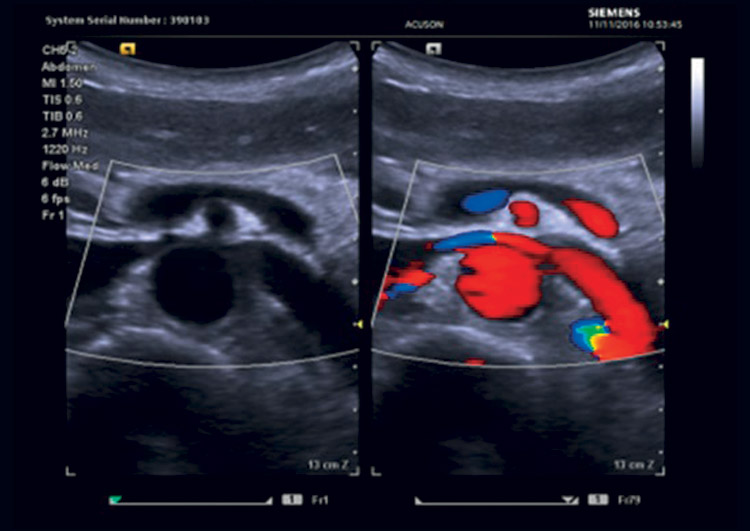

Grazie alla Persistenza Dinamica e all’Auto Flash Suppression, il sistema è in grado di eliminare gli artefatti da movimento nell’utilizzo del color doppler in modo da valorizzare meglio anche i vasi più piccoli

La tecnologia brevettata Vascular Enhancement (VE) utilizza le informazioni del Power Doppler per migliorare notevolmente l’immagine in B-Mode aumentando i dettagli dei tessuti anatomici